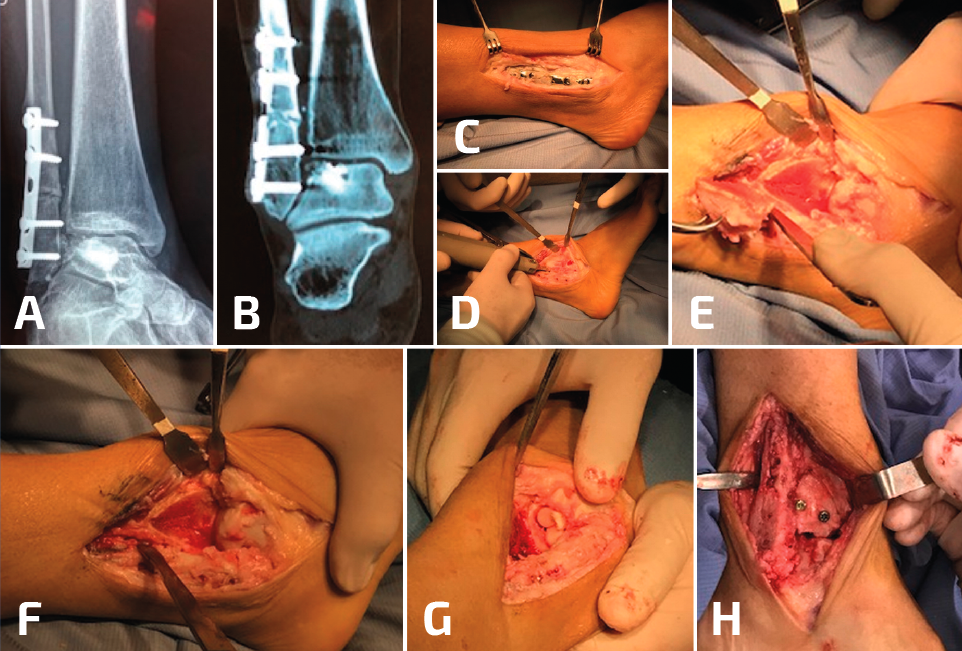

La selección de la osteotomía y el tipo de injerto para la reconstrucción va a depender de la posición de la mala consolidación; recuerden que el peroné puede estar acortado o rotado a externo, o bien acortado y rotado a interno. Idealmente, no sería necesario desprender la sindesmosis en su totalidad para elongar el peroné (Figura 3). Si el peroné está rotado hacia afuera y no está acortado, entonces se puede realizar una osteotomía rotacional sin elongación y, de esta manera, se preserva la sindesmosis, aunque esto no es una condición frecuente. El objetivo del tratamiento de la consolidación viciosa del peroné consiste en restaurar la correcta longitud y la rotación, para obtener una alineación anatómica del astrágalo dentro de la mortaja del tobillo. Sin embargo, también es importante reconocer otros aspectos del patrón original de la fractura.

Figura 3. En este paciente, además de la pseudoartrosis del peroné, se asocia un gran defecto osteocondral del astrágalo (A, B, C). Para acceder a la lesión, se realizó una osteotomía en la región lateral de la tibia (D, E, F). Después de la colocación de los injertos tomados de la rodilla, se realizó la osteosíntesis de la osteotomía de la tibia y posteriormente se trató la pseudoartrosis del peroné (G, H).